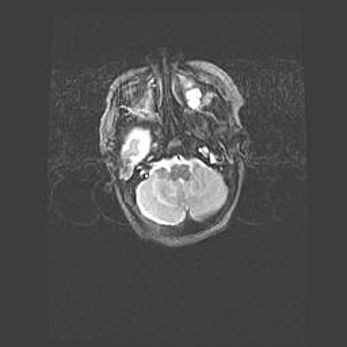

Мальформация Денди-Уокера. Киста задней черепной ямки.

Агенезия мозолистого тела.

Возраст: 2,5 месяца

Вес: 2420 г

Пол: женский

Окружность головы: 37 см

Срок гестации: 32 недели

Мальформация Денди—Уокера — редкий вид патологии ЦНС, представляющий собой врожденный порок развития каудального отдела ствола и червя мозжечка, ведущий к неполному раскрытию срединной (Мажанди) и латеральных (Лушка) апертур IV желудочка мозга. Для этогно синдрома характерна триада симптомов: гипотрофия червя мозжечка и/или полушарий мозжечка, кисты задней черепной ямки, гидроцефалия различной степени. В 70% случаев порок сочетается и с другими аномалиями головного мозга, в частности с агенезией мозолистого тела.